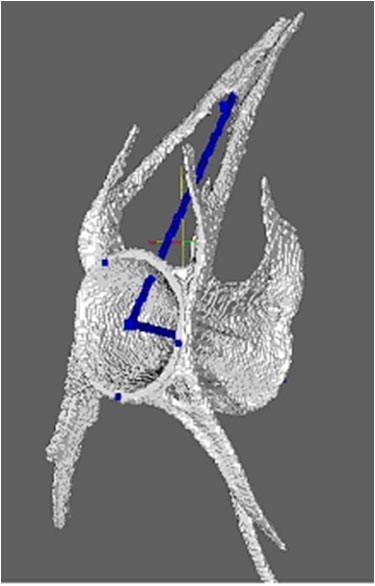

The majority of the work during the past five years has been supported by a successful NIH grant. (R01AR056664). The goal of this study was to develop and validate several software-based measures of knee OA from MRI data sets. Much of the group’s recent effort has been directed at accomplishing the aims of this grant proposal. We now have fast quantitative methods in place for cartilage morphometry (1-2), bone marrow lesion (BML) (3), and osteophyte volume (4), and have looked at associations of these measures with pain. Methods are in place to assess large numbers (several hundred) subjects for multiple disease-related structures, which will facilitate future higher power studies of knee OA. We are actively seeking additional funding to support the next phase of the program.

Additionally we are pursuing several different but related research projects. Methods have been developed and validated to characterize progression the progression of hip and hand OA radiographically (5). In collaboration with Dr. Chris Evans at the Mayo Clinic, Dr. Duryea was recently awarded a supplemental grant to support a study testing the hypothesis that a novel method based on conventional radiography can be used to detect the status of osseous defects with high accuracy. We have also received a NIH grant to support a study to evaluate hand radiography in conjunction with a study of adiposity-related metabolic factors as predictors of incident hand OA. In collaboration with Daniel Solomon in the BWH Rheumatology Division, Department of Medicine we are developing methods to assess hand RA using multi-slice CT. With Drs. Anthony Aliprantis and Matthew Harris, we have initiated a project to apply quantitative methods to assess bone parameters of zebra fish.

Hand CT to evaluate RA erosions |